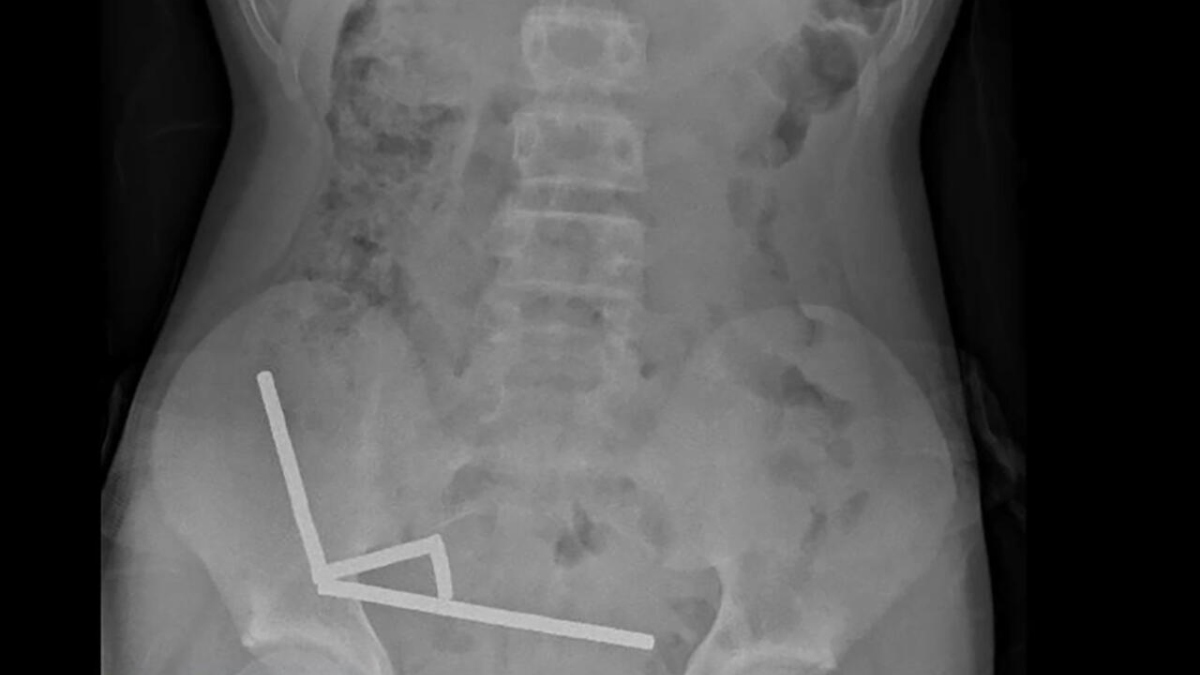

An X-ray showed the magnets had formed four linear clusters inside the boy’s intestines. “These appeared to be in separate parts of bowel adhered together due to magnetic forces,” the doctors said. The attraction between the magnets caused tissue death, or necrosis, in multiple areas of the small bowel and caecum.